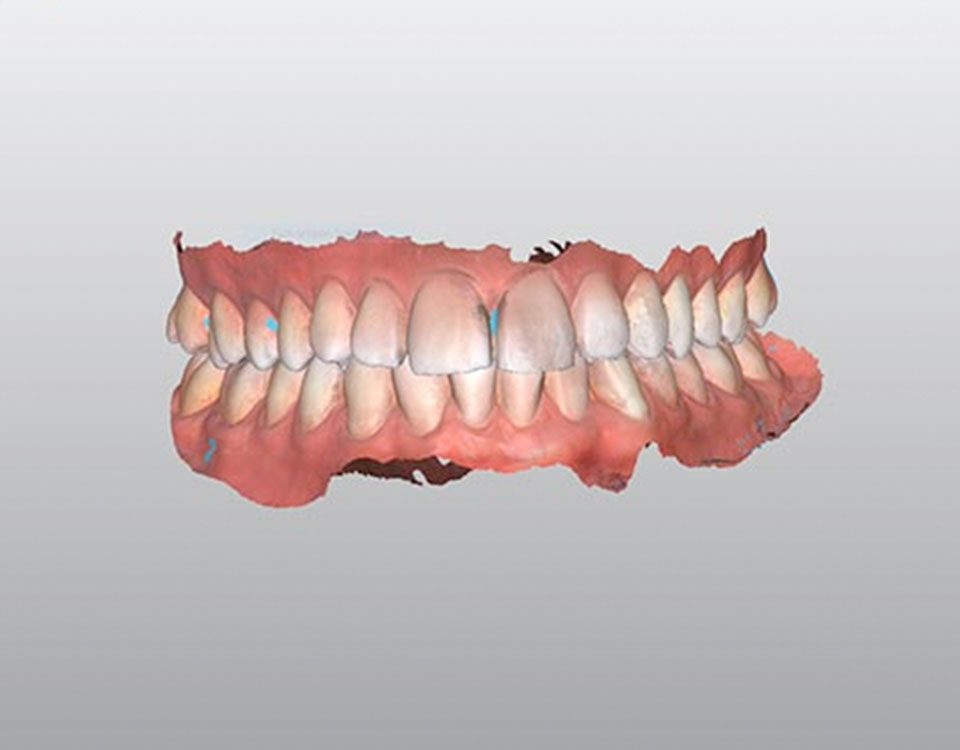

Scanner Intra-oral

O Scanner intra-oral é um dispositivo eletrónico que reproduz as estruturas anatómicas da cavidade oral em 3D, permitindo que o Médico Dentista mostre ao paciente como vão ficar os seus dentes antes de os tratar. Muitas vezes até é possível experimentar em boca um protótipo do que será o fim do tratamento.